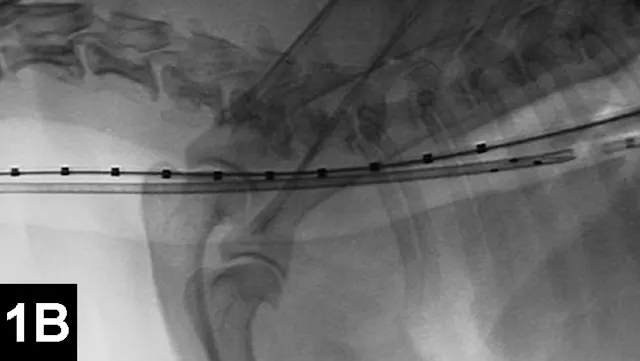

IR techniques that involve placement of an intraluminal stent to alleviate signs associated with malignant obstructions have been described in veterinary patients (Figure 2).5 The author has performed multiple palliative stenting procedures in the urinary tract and upper and lower GI tracts and has relieved luminal obstructions caused by neoplasia or intractable benign strictures in many different sizes of animals, including ferrets.5-11 The IR techniques were fast, safe, and effective. Complications were minor and uncommon.

Figure 2A: Serial lateral positive contrast urethrocystograms in a dog with a malignant urethral obstruction secondary to a prostatic tumor.

Maximal urethral diameters measured using a colonic marker catheter to adjust for radiographic magnification.